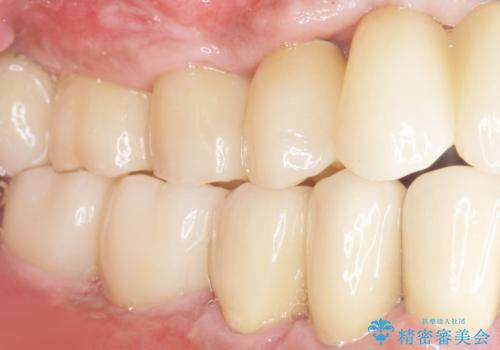

再生療法と骨外科処置により、歯周ポケットは全周2mm以下に改善されました。

保存が難しいと思われた歯を残すことができ、患者様にご満足頂けました。

歯周病治療と連結補綴により歯の動揺がなくなり、「なんでも食べられます!」と喜んで下さいました。

クラウンの種類:メタルボンドクラウン エコノミー